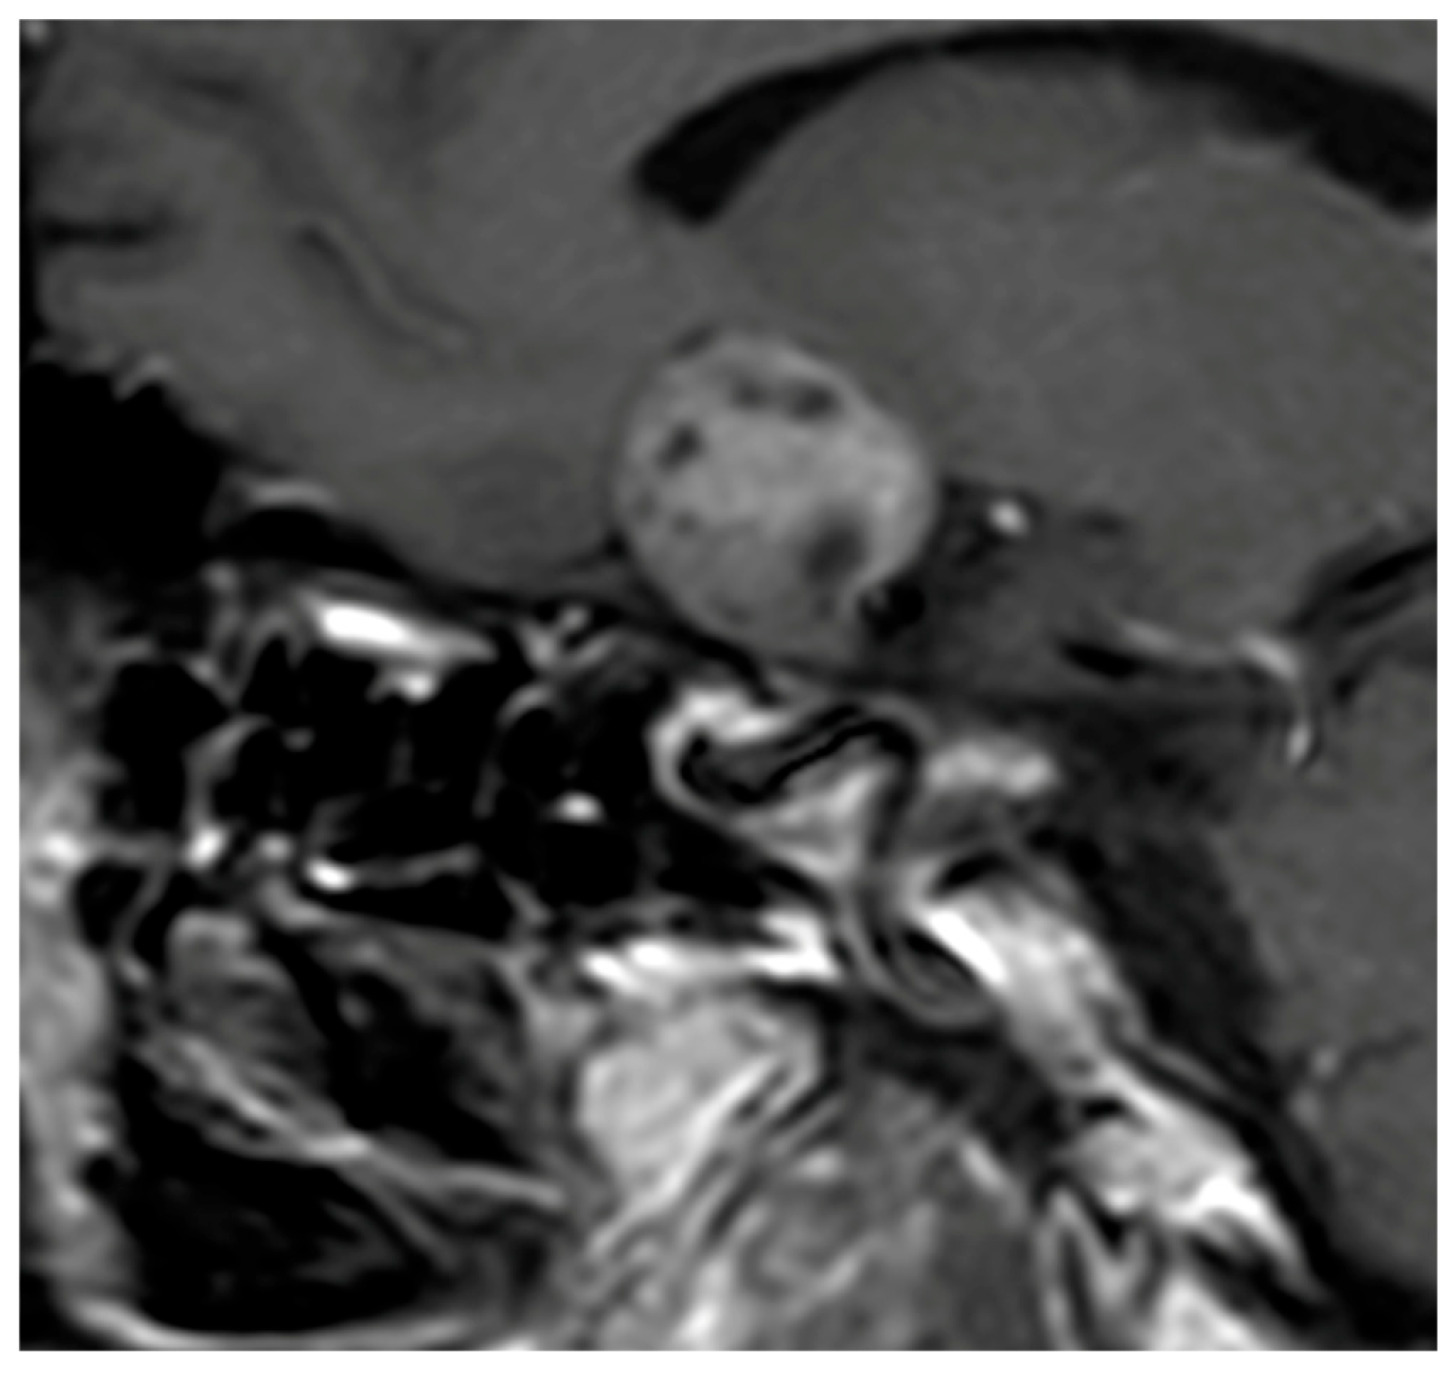

In most series, the tumor volume constitutes one of the most reliable discriminative variables. Hypophysitis typically presents with a moderate and diffuse enlargement of the pituitary gland, in contrast to the more expansive and space-occupying lesions of NFPMA. Gutenberg et al. [37] reported mean volumes around 3 cm3 for hypophysitis compared to 10 cm3 for NFPMA, identifying a threshold of approximately 7 cm3 as particularly useful for distinction. Subsequent studies, including those of Wright et al. [38] and Ach et al. [39], have confirmed this tendency, with mean volumes of 1.45 cm3 and 7.16 cm3, respectively, for hypophysitis and NFPMA (Figure 1).

Signal characteristics on MRI further reinforce this opposition. Hypophysitis usually exhibits an isointense signal on both T1- and T2-weighted sequences [70,71], indicative of homogeneous inflammatory tissue without necrosis or cystic degeneration. In contrast, NFPMA often show variable signal intensities, with possible T1 hypersignal due to intratumoral hemorrhagic components [37] and frequent T2 hyperintensity related to cystic or necrotic transformation [37,72]. Flanagan et al. [8] and Wright et al. [38] reported T2 hypersignal in only 5 to 8% of hypophysitis, as opposed to 25% in macroadenomas, underscoring the relative uniformity of inflammatory lesions (Figure 2).

Figure 1. Sagittal T1-weighted image after Gadolinium injection showing a heterogeneous enhancement of the pituitary mass consistent with a NFPMA.